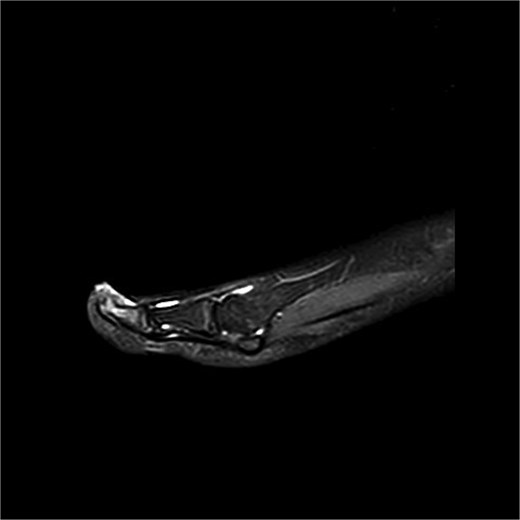

A 12-year-old male presented with pain and deformity of the right great toe (Fig. 1). MRI confirmed SE with osteomyelitis (Fig. 3). Bone cultures grew S. aureus and Staphylococcus lugdunensis with moderate growth in one of five samples. After 1 week of intravenous therapy, treatment was completed with oral dicloxacillin. At 17- and 39-day follow-up visits, the patient was pain-free with no signs of infection (Fig. 2).

Preoperative MRI from case 1 demonstrating SE and associated bone marrow edema.